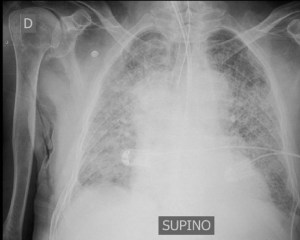

La COVID-19 è una malattia caratterizzata da una polmonite con infiltrati interstiziali, che rientra a pieno nella definzione di ARDS: è una condizione acuta con ipossiemia grave e infiltrati polmonari bilaterali non attribuibile ad una disfunzione ventricolare sinistra. Ma dal punto di vista ventilatorio ha qualche peculiarità rispetto alle ARDS a cui siamo abituati.

Nei casi che ho seguito la caratteristica principale è la grave ipossiemia associata ad una compliance dell’apparato respiratorio superiore a quella che normalmente vedo nei casi di grave ARDS.

Nella mia personale esperienza, il paziente “tipo” con COVID-19, che ha una gravissima disfunzione polmonare, con un PaO2/FIO2 di circa 100 mmHg (anche meno), ed una meccanica respiratoria solo lievemente peggiore di quella dei pazienti ventilati senza ARDS, con una compliance dell’apparato respiratorio di circa 40 ml/cmH2O. Si ha quindi spesso a che fare con un paziente gravemente ipossico ma “facile” da ventilare. La compliance quantifica quanti ml di gas entrano nei polmoni aumentando di 1 cmH2O la pressione nelle vie aeree: se la compliance è 40 ml/cmH2O, saranno necessari 10 cmH2O per erogare un volume corrente di 400 ml (cioè circa i 6 ml/kg di peso ideale). Questi 10 cmH2O sono la driving pressure, che ha un valore ritenuto di assoluta sicurezza (ben al di sotto dei 14-15 cmH2O).